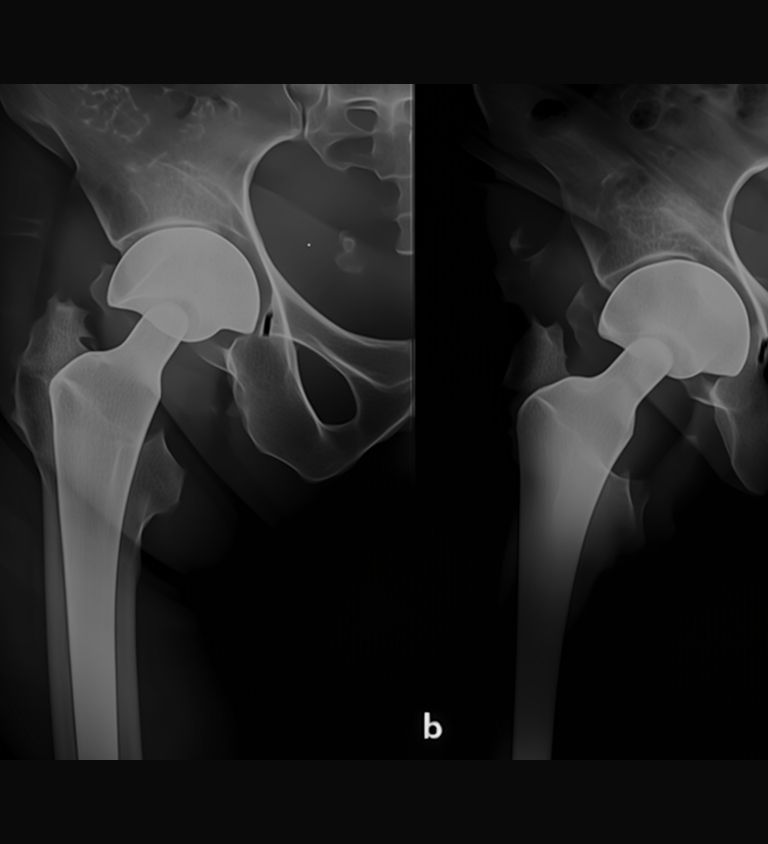

Unipolar Hemiarthroplasty Surgery

Bipolar Hemiarthroplasty Surgery